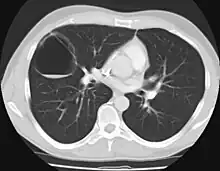

CPAMs are classified into three different types based largely on their gross appearance. Type I has a large (>2 cm) multiloculated cysts. Type II has smaller uniform cysts. Type III is not grossly cystic, referred to as the "adenomatoid" type. Microscopically, the lesions are not true cysts, but communicate with the surrounding parenchyma. Some lesions have an abnormal connection to a blood vessel from an aorta and are referred to as "hybrid lesions."

The earliest point at which a CPAM can be detected is by prenatal ultrasound. The classic description is of an echogenic lung mass that gradually disappears over subsequent ultrasounds. The disappearance is due to the malformation becoming filled with fluid over the course of the gestation, allowing the ultrasound waves to penetrate it more easily and rendering it invisible on sonographic imaging. When a CPAM is rapidly growing, either solid or with a dominant cyst, they have a higher incidence of developing venous outflow obstruction, cardiac failure and ultimately hydrops fetalis. If hydrops is not present, the fetus has a 95% chance of survival. When hydrops is present, risk of fetal demise is much greater without in utero surgery to correct the pathophysiology. The greatest period of growth is during the end of the second trimester, between 20–26 weeks.